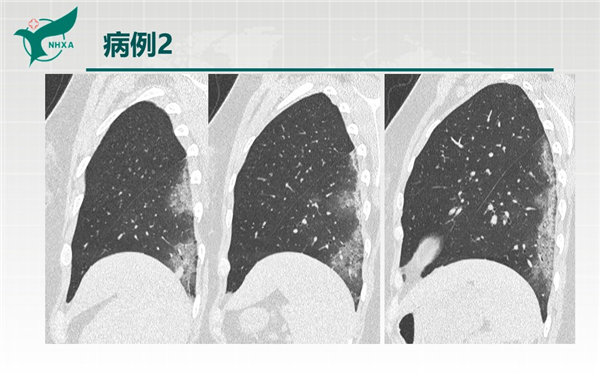

幻燈片6.jpg